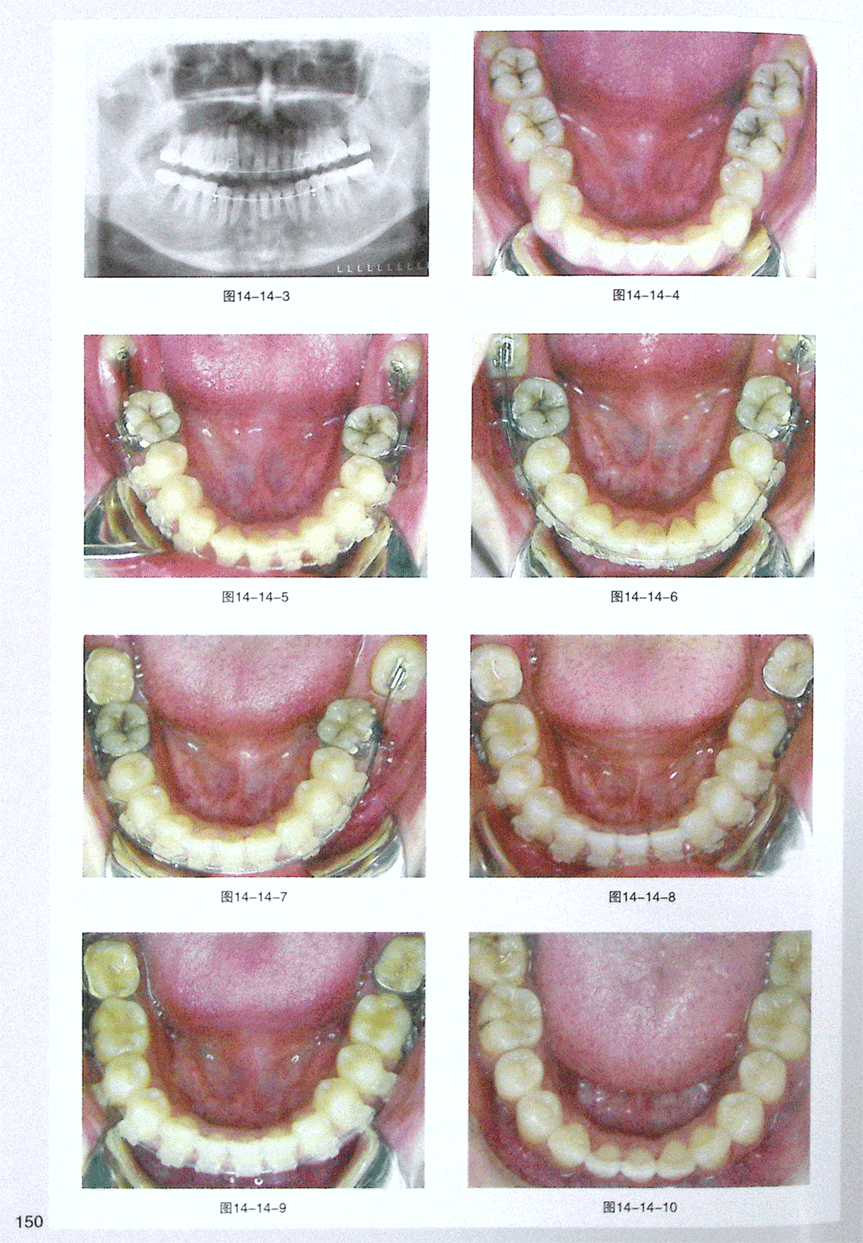

第十四节 正畸手段竖直水平阻生智齿